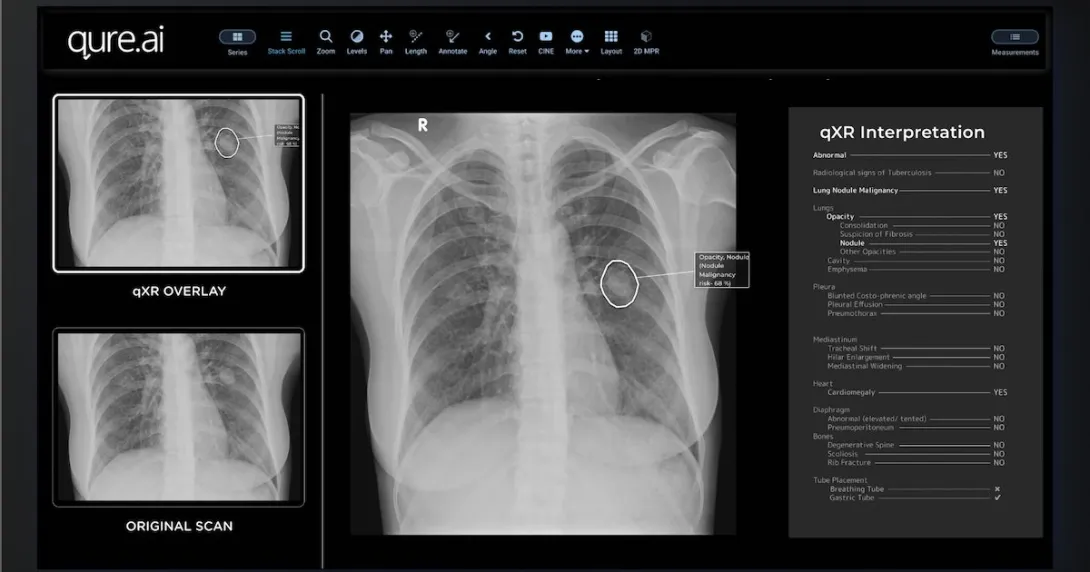

According to a press statement, MyBeam is a compact, lightweight device equipped with high-frequency technology for detecting TB. It will be powered by Qure.ai's deep-learning software qXR to analyse chest x-ray images and identify TB within a minute.

This is not the first time that the qXR, a WHO-recommended and CE-marked solution for the preliminary detection of TB, has been used to support the expansion of TB screening in India. In 2021, Fujifilm India started collaborating with Qure.ai to integrate its AI software into the Fujifilm X-ray FDR Xair system.